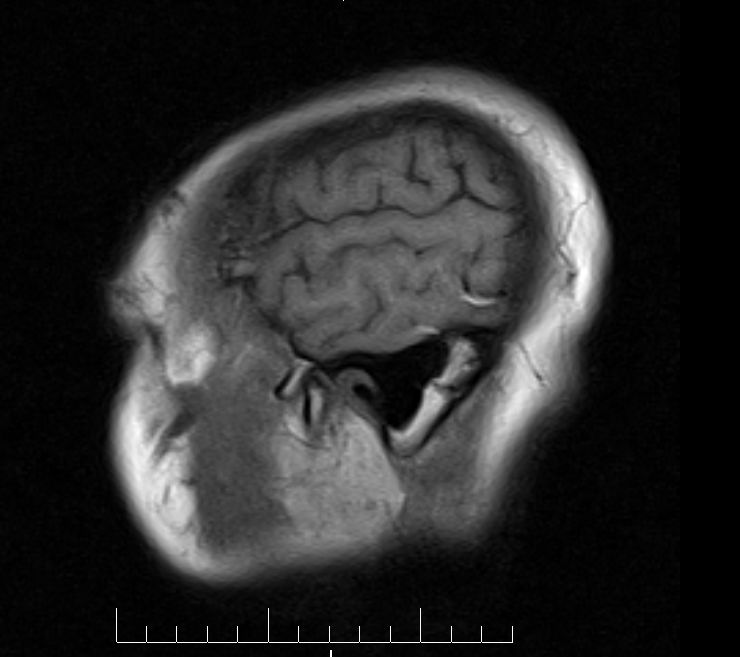

标题: MRI2379:30岁,男,癫痫10年,请各位看一下;CT示:左颞叶钙 [打印本页]

标题: MRI2379:30岁,男,癫痫10年,请各位看一下;CT示:左颞叶钙

左颞叶区见不规则点状混杂信号影

支持2楼 左颞叶区见不规则点状混杂信号影,考虑动静脉畸形。

考虑左侧颞叶脑血管畸形(avm)。----t1低等高混杂信号,t2等高信号周边较多流空血管影[冠状位明显],mra左侧大脑中动脉受压,远侧聚集.